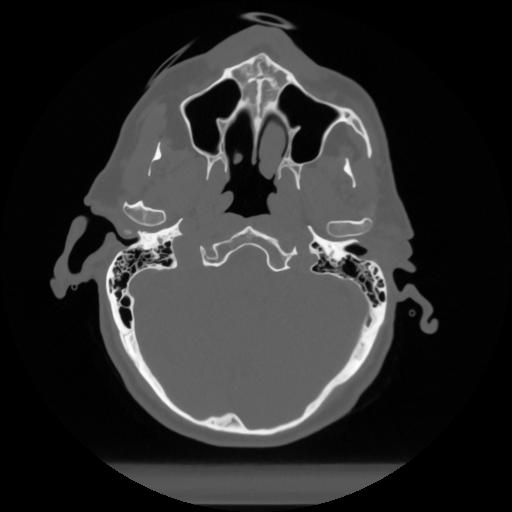

12 P.BLANDAS,,Vol,0.5,P.BLANDAS,,